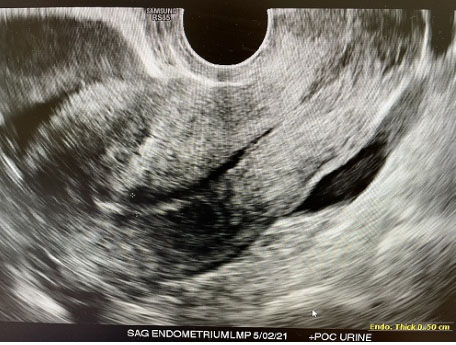

Figure 2: Sagittal transvaginal US of uterus revealing no intrauterine pregnancy (IUP) and free fluid seen in pouch of Douglas.

A 25-year-old gravida 1, para 0 at 5 weeks+0 day by last menstrual period (LMP) initially presented to emergency room with worsening lower abdominal pain for two days. No significant past medical history. Physical exam revealed guarding and generalized abdominal pain and rebound. At that time, patient vitals were unremarkable, Temperature: 98°F, blood pressure (BP): 106/67 mmHg, pulse rate: 88 bpm, respiratory rate (RR): 18 breaths per minute, SpO2: 100% on room air (RA). Laboratory evaluation revealed the patient had a positive β-hCG 1444 mIU/mL and hemoglobin/hematocrit of 12.0 g/dL/38.0%. Pelvic ultrasound (US) revealed no intrauterine pregnancy and thick walled right adnexal ring measuring 2.6 cm with low level internal echos, and moderate amount of complex pelvic fluid (Figure 1 and Figure 2). The patient was taken to operating room which revealed extensive hemoperitoneum of 800 mL of blood and clots, normal uterus and intact bilateral fallopian tubes, and a 2 cm vascular cystic gestational sac-like structure which was attached to omentum and to fimbria of right fallopian tube, that was mixed with clots (Figure 3). Intraoperative general surgery consult was called due to proximity to bowel, it was noted that the gestational sac and omentum were free of bowel, a transection and wedge resection was performed on the affected area. The specimen was sent for pathological evaluation revealing the presence of focal trophoblasts and chorionic villi (Figure 4). The patient serum hCG was followed outpatient till negative.